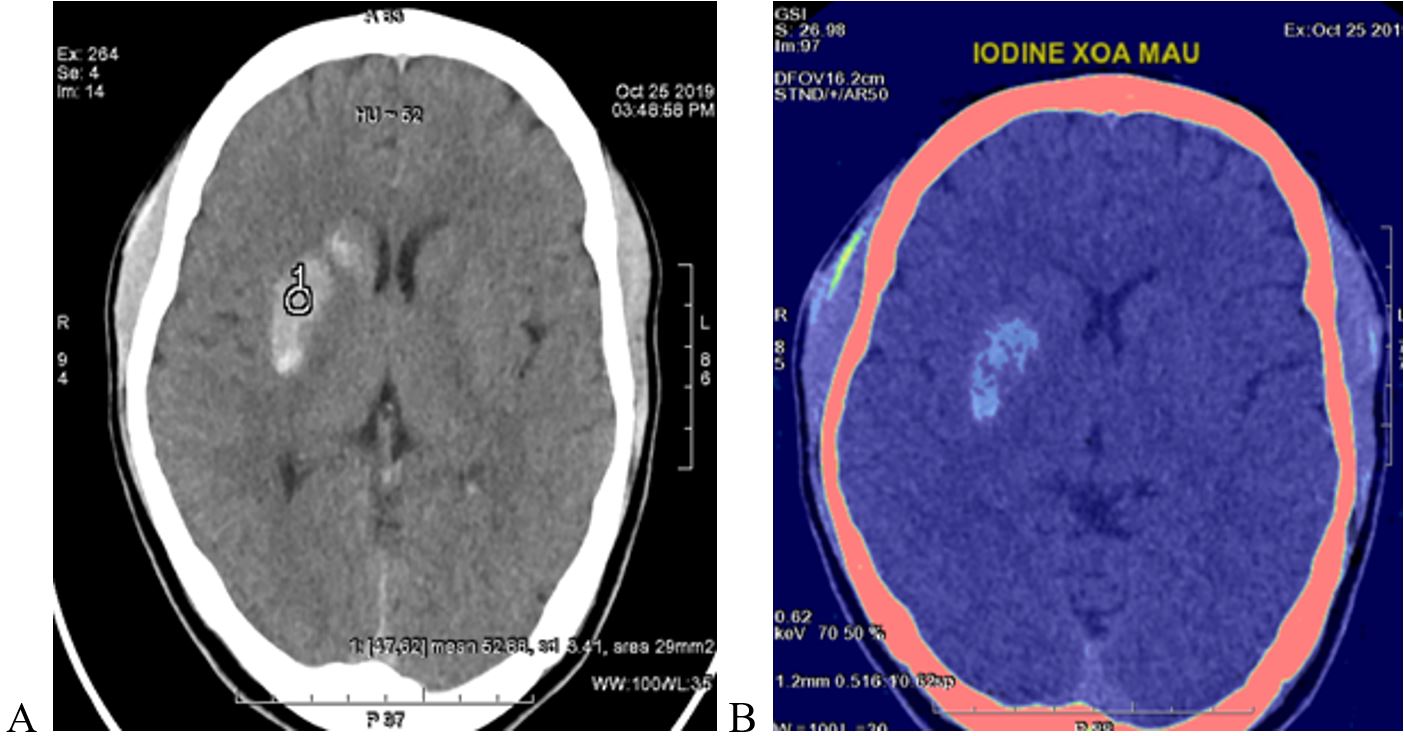

Hình 1. Hình ảnh chụp CLVT sọ não đánh giá sau can thiệp mạch

Trên hình 1, bệnh nhân sau can thiệp mạch được tiến hành chụp CLVT sọ não để đánh giá. Trên cửa sổ nhu mô não (hình A) thấy đám tăng tỷ trọng ở nhân xám trung ương bên phải. Đặt ROI vào vùng tổn thương đo tỷ trọng không thể phân biệt được là máu hay thuốc cản quang thoát mạch. Chụp CLVT phổ trên máy CLVT Revolution CT 512 dãy có thể dùng các cặp vật chất để xác định điều này một cách chính xác.

Ở hình B, sử dụng hình ảnh I-ốt có xóa máu, nhận thấy đám tăng tỷ trọng vẫn hiện ảnh, đây là i-ốt có trong thuốc cản quang. Vì vậy, trường hợp này được xác định không phải chảy máu não mà là thuốc cản quang đã sử dụng trong quá trình can thiệp mạch.